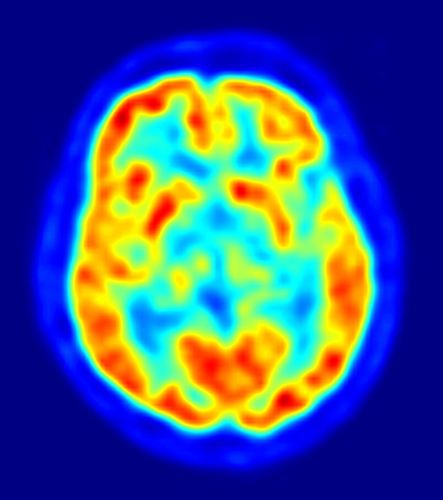

Investigadores de la Universidad McGill, en Canadá, y la Universidad Carlos III de Madrid han detectado actividad del cerebro embrionario antes del nacimiento en experimentos* realizados en embriones de pollos. Estos hallazgos podrían tener implicaciones en el estudio del desarrollo de animales, así como de los nacidos prematuramente.

Según este estudio, publicado en la revista ‘Current Biology’, bajo ciertas condiciones, los cerebros de los pollos embrionarios parecen estar activos mucho antes de que estén listos para romper el cascarón y salir de sus huevos. Los investigadores despertaron embriones de pollo, dentro de sus huevos, mediante la reproducción de sonidos fuertes y significativos para ellos (la reproducción de sonidos sin sentido para los pollos no fue suficiente para despertar sus cerebros).

“Este trabajo muestra que los cerebros de los embriones pueden funcionar de una manera activa, antes de lo previsto -mucho antes del nacimiento“, declara Evan Balaban, de la Universidad McGill, en Canadá. “Al igual que los cerebros adultos, los cerebros de los embriones también poseen conexiones neuronales, que controlan el medio ambiente para despertar el cerebro, de manera selectiva, durante los eventos importantes”.

Estos hallazgos podrían explicar los casos de aprendizaje fetal y neonatal, planteando nuevas preguntas acerca de las consecuencias en el desarrollo a largo plazo de la actividad cerebral en los bebés, de cualquier especie, que nacen muy prematuramente.